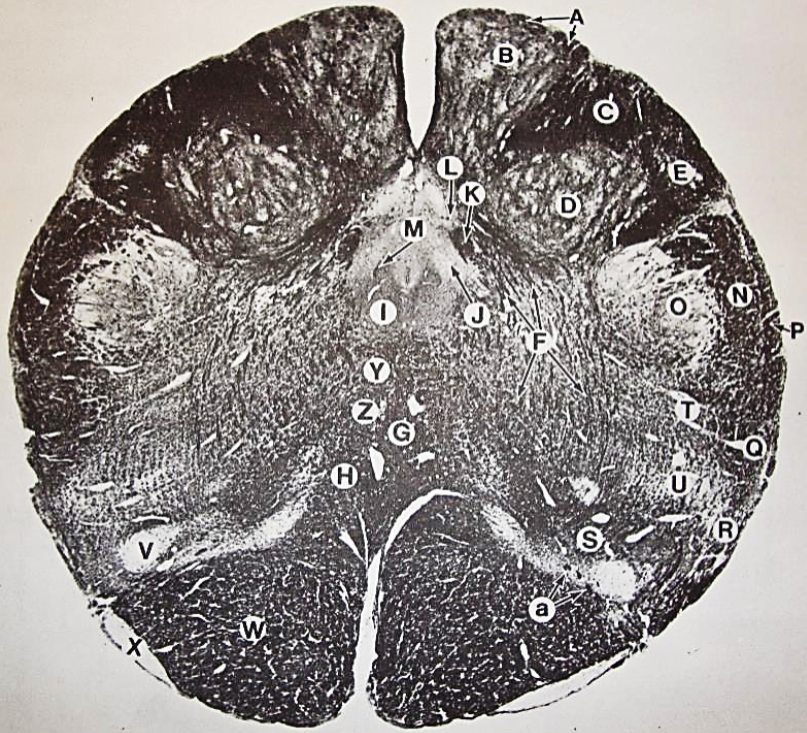

A

fasciculus gracilis

B

gracile nucleus

C

fasciculus cuneatus

D

cuneate nucleus

F

internal arcuate fibers

G

decussation of internal arcuate fibers

H

medial lemniscus

I

hypoglossal nucleus

J

dorsal motor nucleus vagus

K

solitary fasciculus

L

solitary nucleus

M

dorsal longitudinal fasciculus

N

spinal trigeminal tract

O

spinal trigeminal nucleus

P

posterior spinocerebellar tract

Q

anterior spinocerebellar tract

R

spinal lemniscus

S

lateral vestibulospinal tract

T

rubrospinal tract

U

lateral reticular nucleus

V

medial accessary olivary nucleus

W

pyramidal (corticospinal) tract

X

arcuate nucelus

Y

medial longitudinal fasciculus

Z

tectospinal tract

a

fascicles of hypoglossal nerve